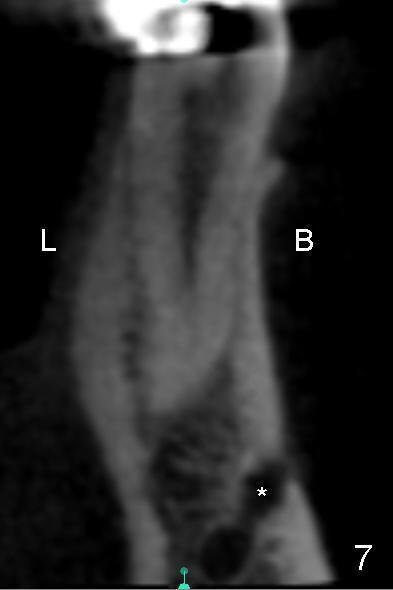

下颌第二前磨牙CT矢状切面显示近远中宽四毫米(图六),冠状切面显示颊(图七B)舌(L)侧宽约六毫米(图八),颏神经襻(*)颊侧比舌侧高,如果即刻植牙偏向舌侧(图九红色),颏神经受损可能性减少。如果即刻植牙局限于拔牙窝(图九虚线),那么更安全(1 2)。